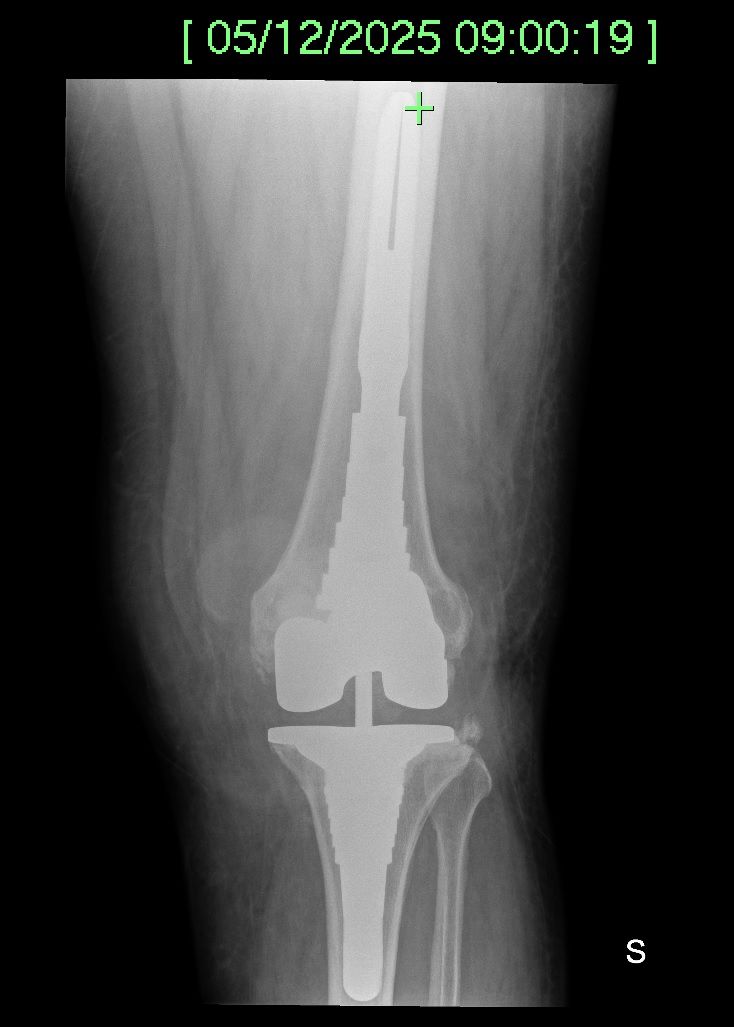

Foto e video